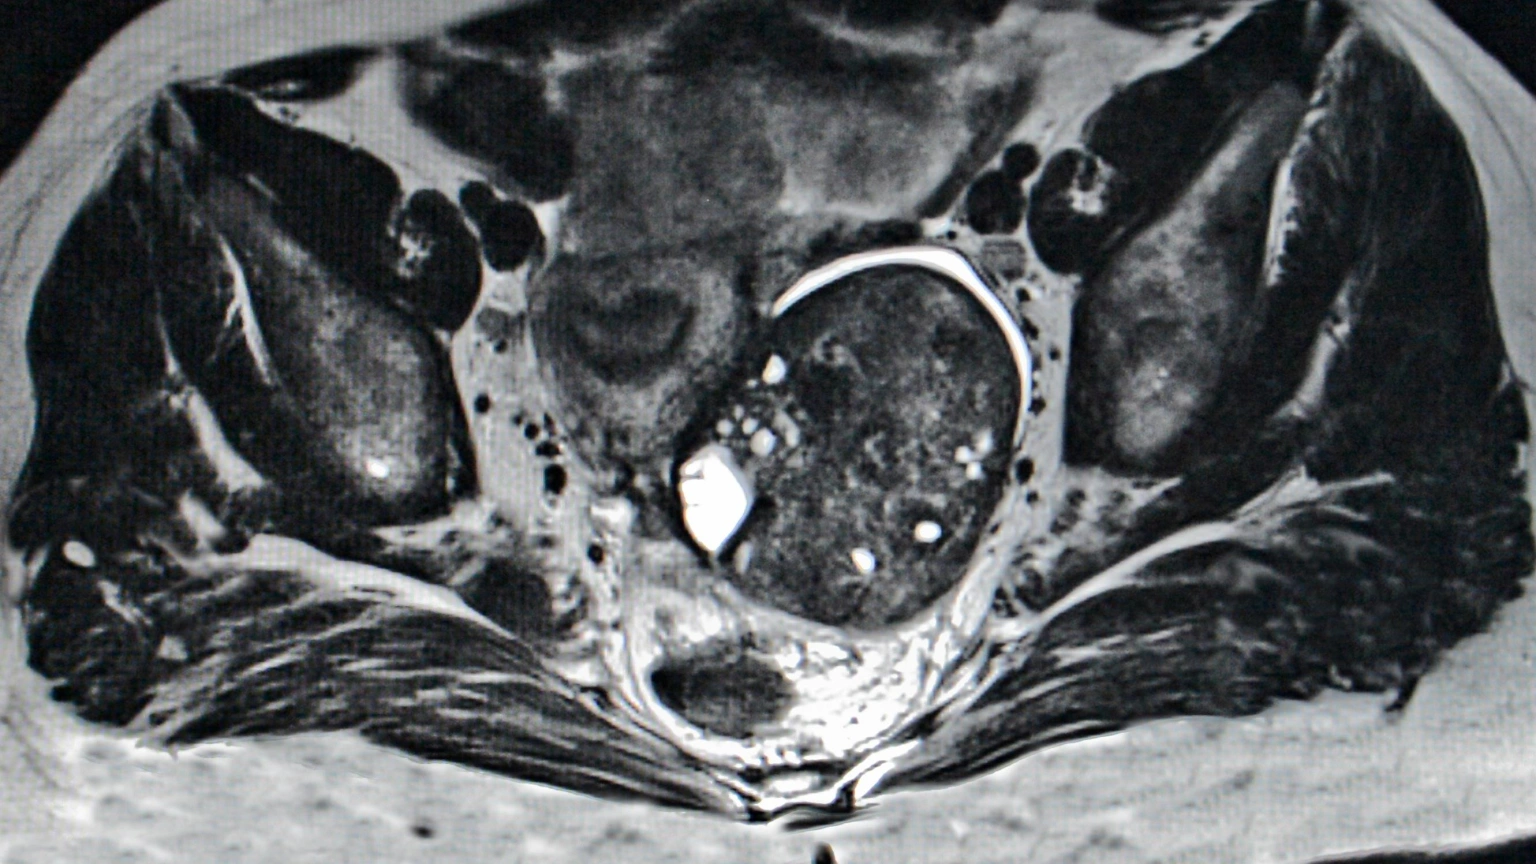

Imagen de recurso

"Lo que se ha realizado es un análisis exploratorio de la supervivencia de pacientes que se incluyeron en el estudio y a la vez estaban tomando estatinas", agrega.

Explica el doctor González que dentro del estudio participaron un total de 728 pacientes, a las que dividieron en cuatro grupos: el primero con niraparib con estatinas; placebo con estatinas; niraparib sin estatinas y placebo sin estatinas.

Se ha demostrado que "las pacientes que recibieron niraparib junto con estatinas presentaron una mejor supervivencia libre de progresión en comparación con aquellas que recibieron placebo más estatinas". Un beneficio, agrega, que "fue menor en las pacientes que no tomaron estatinas".